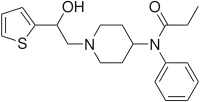

Anilidopiperidines